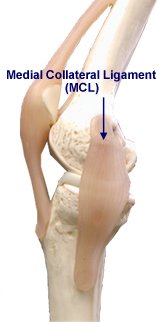

Please annotate this diagram with the site(s) of swelling or tenderness.

Right Knee

Notes: -

Left Knee

Notes:-

Is there detectable instability: Yes / No

This is notoriously difficult to assess immediately after injury as pain inhibition limits the passive envelope of movement of the knee.

Notes:-